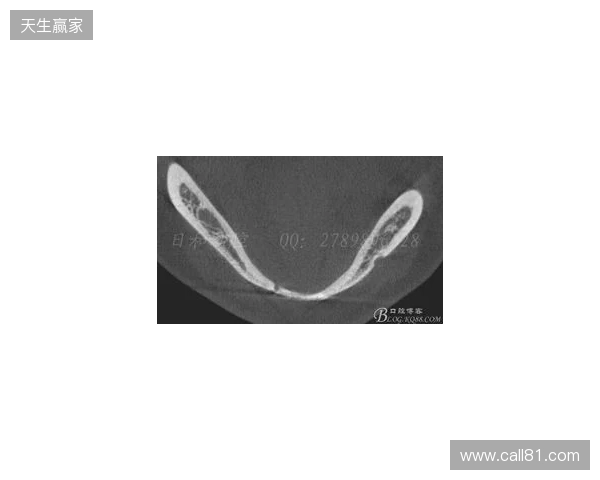

韦林顿确诊上唇部贯通伤;11、21牙半脱位;上颌前牙区牙槽骨骨折

根据医院的检查结果,韦林顿·席尔瓦的上唇部受伤程度较为严重,属于贯通伤,已经进行了清创缝合。这种类型的伤势不仅影响外观,还可能对球员的饮食和发声造成影响。更为严重的是,他的上颌前牙区还出现了骨折,意味着席尔瓦在恢复期间将面临长时间的治疗和康复过程。

球员的第11和第21牙出现了半脱位的情况,这可能会导致他在恢复后需要进行进一步的牙科治疗,甚至有可能影响到他今后的职业生涯。医生表示,虽然通过手术和治疗可以恢复,但心理层面的恢复同样重要。